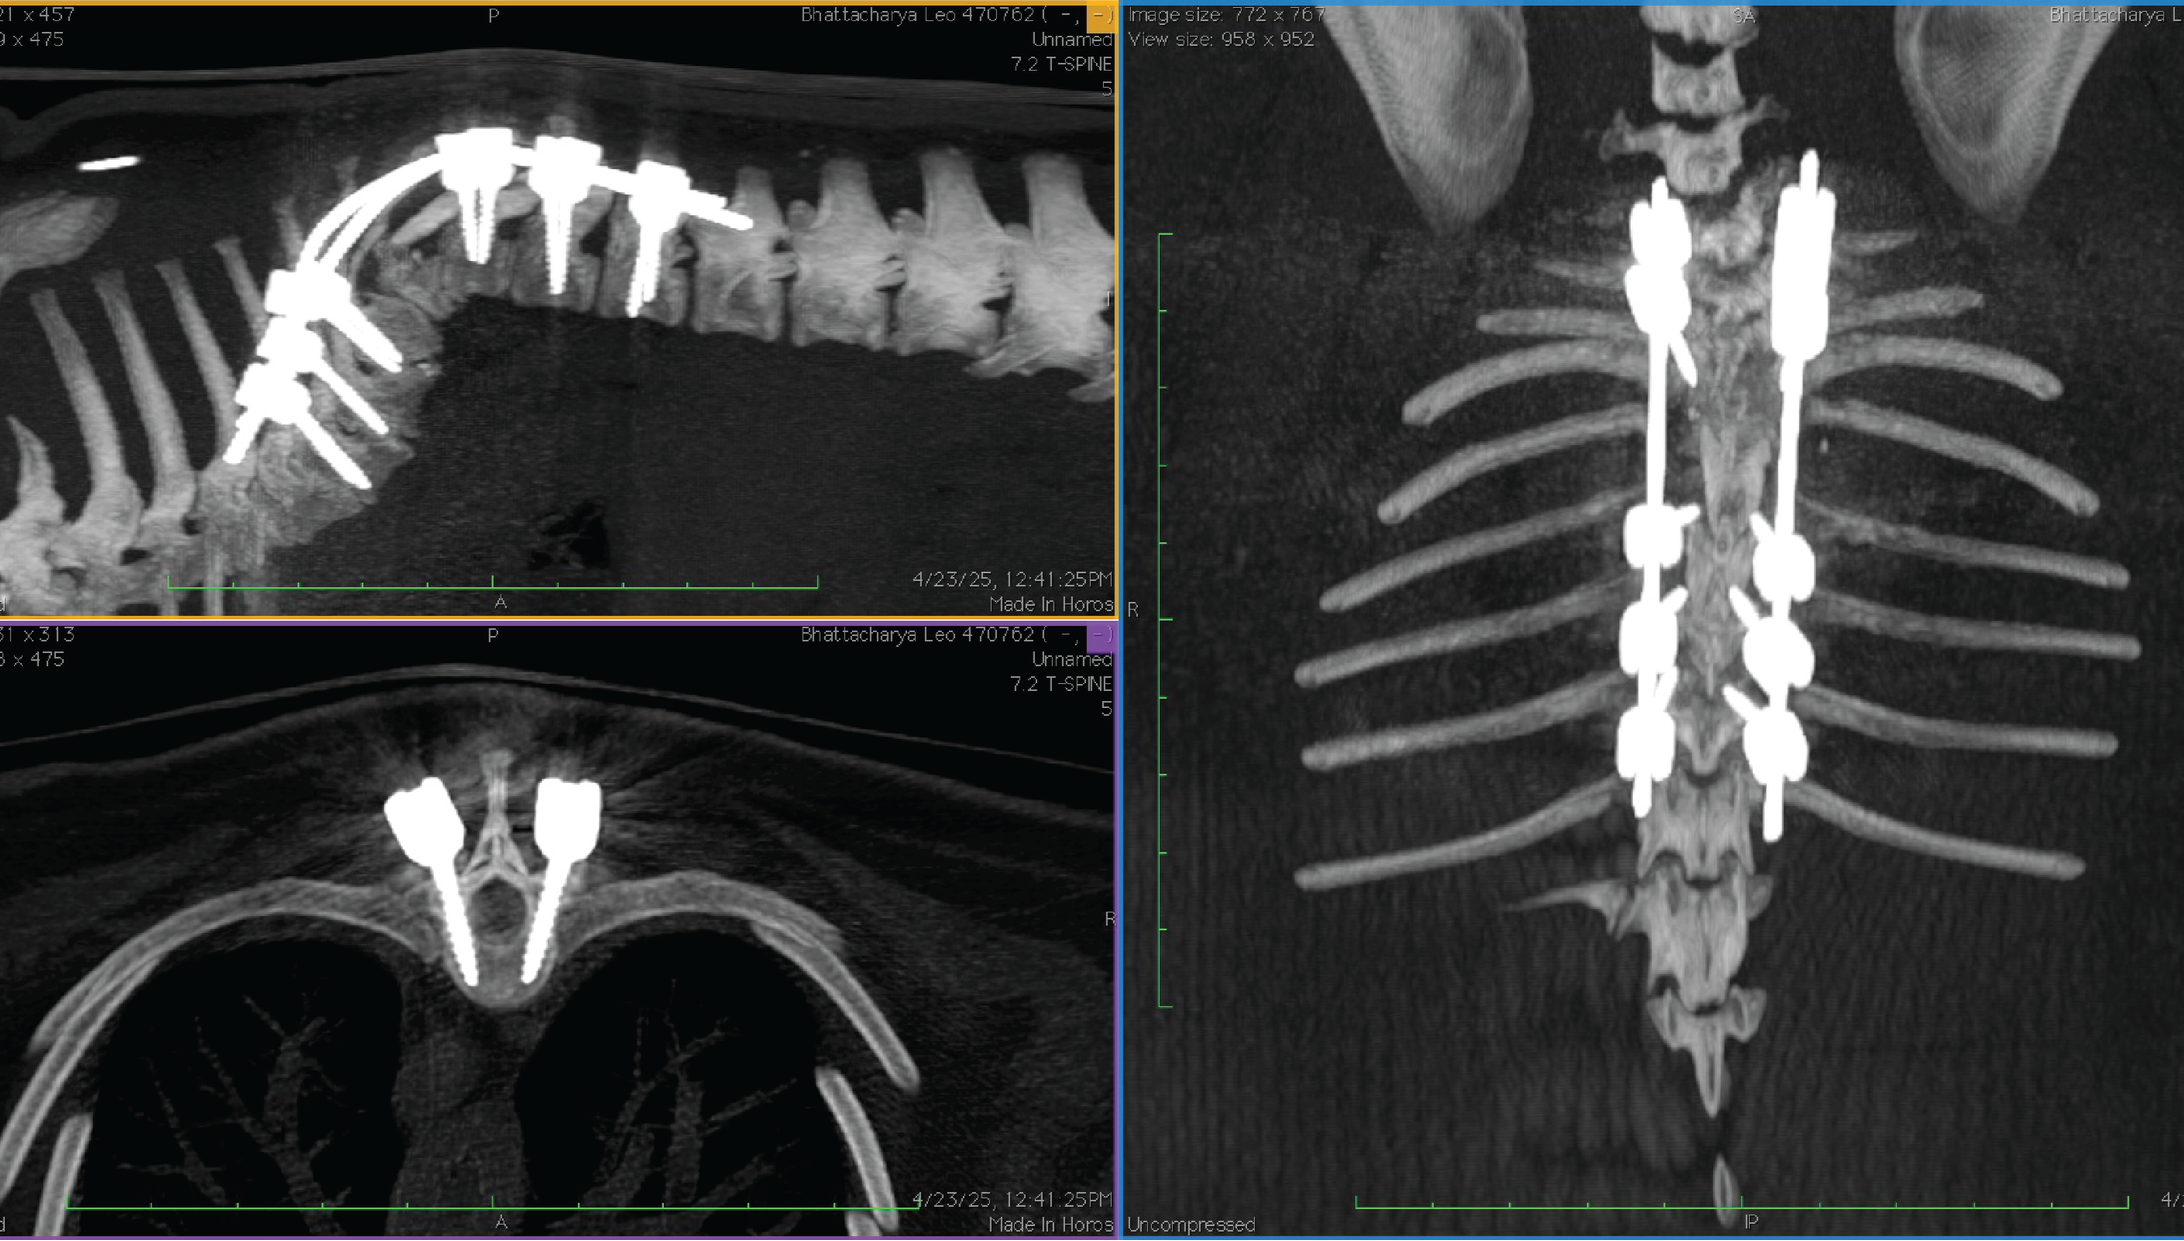

5 kg Pug subtotal corpectomy with stabilization

7 kg French Bulldog dorsal laminectomy with stabilization

8 kg Shih Tzu, C5 - C7 stabilization

8 kg French Bulldog, dorsal laminectomy and stabilization